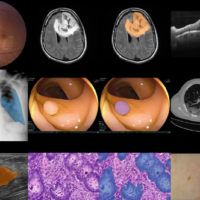

Discover how BiomedParse redefines biomedical image analysis, tackling complex shapes and scaling new heights in precision and efficiency across nine imaging modalities! Study: A foundation model for joint segmentation, …

Researchers explore how AI-driven tumor-infiltrating lymphocyte (TIL) assessments outperform manual methods in precision but stress the need for robust datasets to ensure reliability in clinical practice. Digital image analysis …